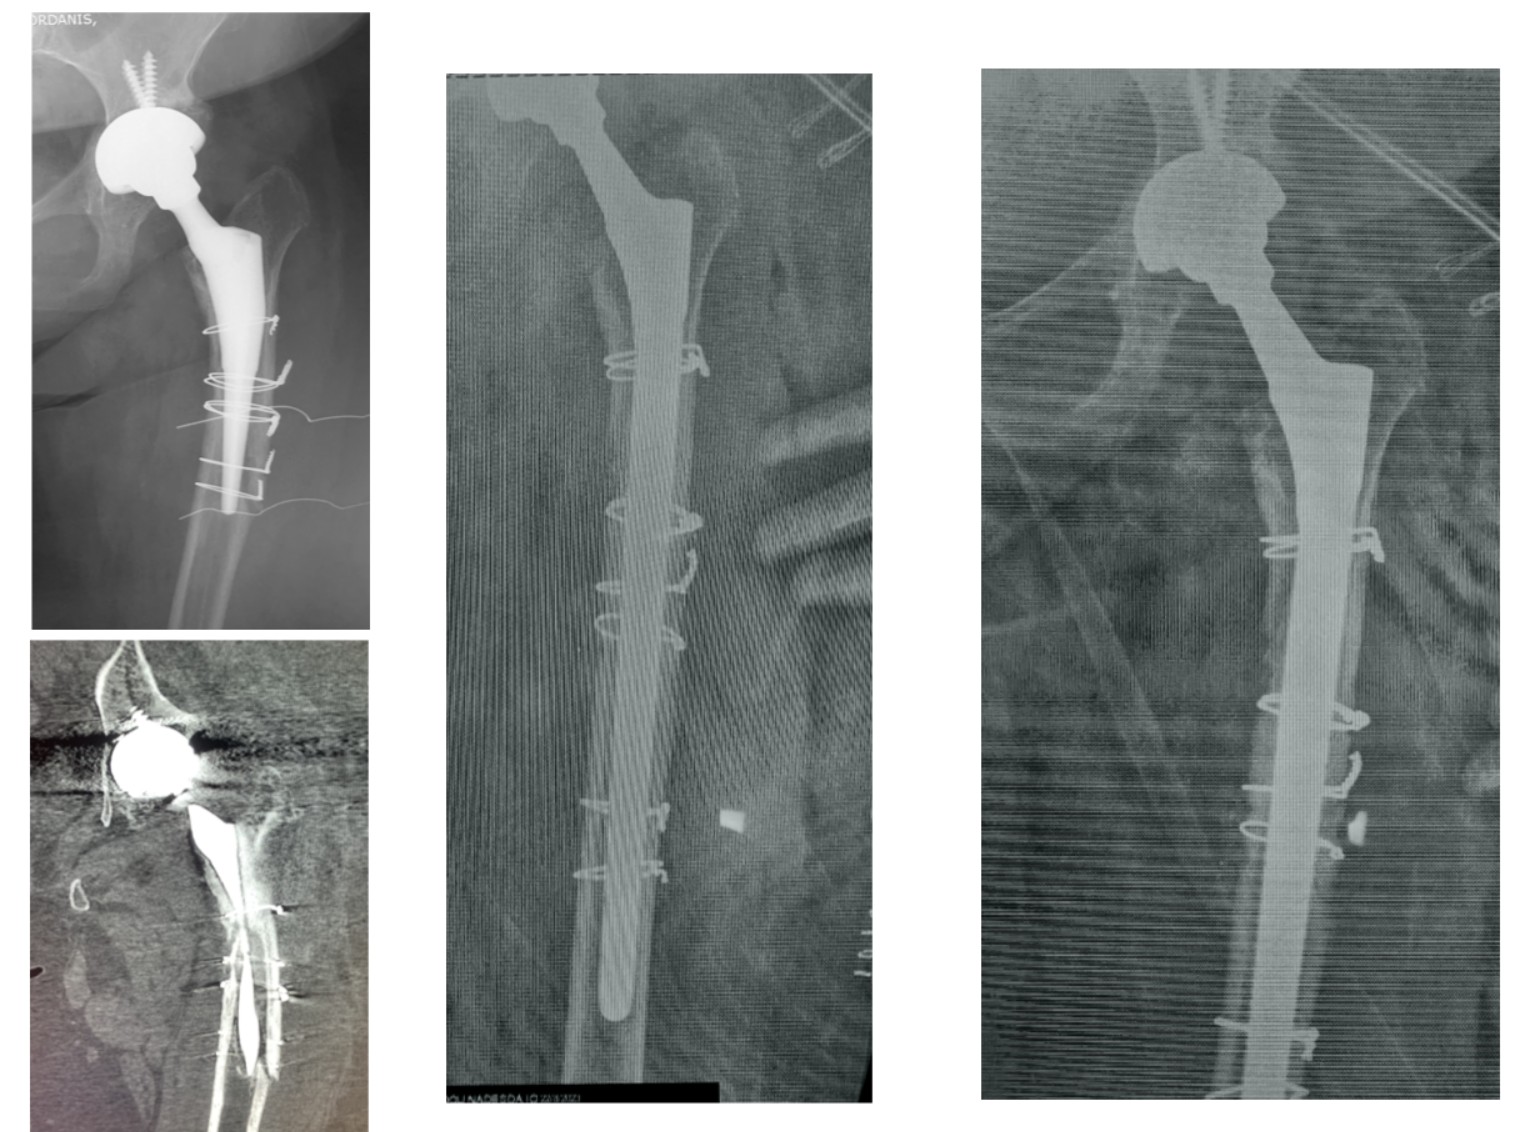

Στην εικόνα 3, ασθενής που κατά την αρχική της  επέμβαση υπέστη κάταγμα μηριαίου. Αντιμετωπίσθηκε λανθασμένα με τοποθέτηση συρμάτων τα οποία δε συγκράτησαν το κάταγμα. Λίγες εβδομάδες μετά, την αντιμετωπίσαμε με αναθεώρηση του μηριαίου στυλεού με ένα ειδικού τύπου μακρύ στυλεό και πολλαπλά σύρματα. 2 χρόνια μετά βαδίζει χωρίς ενοχλήματα.

Στην εικόνα 4, κακή τεχνική οστικού τσιμέντου στη κοτύλη ΚΑΙ στο μηρό. Αποκόλληση ολόκληρης της κοτύλης, κάταγμα στο μηρό και εξάρθρημα, μόλις 2 μήνες μετά την επέμβαση. Αναθεώρηση με τοποθέτηση κοτύλης πορώδους τανταλίου και μακριά πρόθεση μηρού, με άριστο αποτέλεσμα, βάδιση χωρίς πόνο και χωρίς αστάθεια